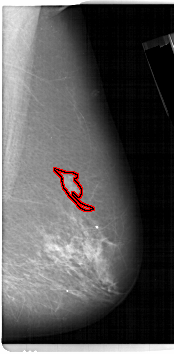

FILE: A_1144_1.RIGHT_MLO.OVERLAY

TOTAL_ABNORMALITIES 1

ABNORMALITY 1

LESION_TYPE MASS SHAPE IRREGULAR MARGINS ILL_DEFINED

ASSESSMENT 4

SUBTLETY 4

PATHOLOGY MALIGNANT

TOTAL_OUTLINES 1

BOUNDARY